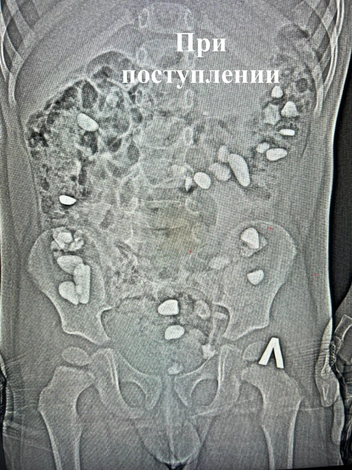

Трехлетний ребенок из Ессентуков проглотил более 25 камней

Необычный случай произошел в Ессентуках: в городскую клиническую больницу доставили трехлетнего мальчика с жалобами на сильные боли и вздутие живота.

Как сообщили в медучреждении, детский хирург назначил рентген, и на снимке врачи увидели то, чего никто не ожидал: в проекции толстой кишки находились десятки мелких инородных тел. Позже выяснилось, что ребенок проглотил более 25 камней. Родители мальчика не смогли объяснить, когда именно это произошло. Медики предполагают, что малыш мог сделать это во время прогулки или игры на улице.

Врачи назначили курс очистительной и противовоспалительной терапии и в течение пяти дней наблюдали за состоянием ребенка. К счастью, хирургического вмешательства не потребовалось: все камни вышли естественным путем, а состояние мальчика значительно улучшилось.